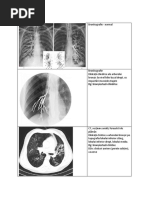

Radiologie.

Radiografia toracică standard are o sensibilitate moderată (88%) și o

specificitate oarecum scazută (74%) pentru detectarea bronșiectaziilor.

radiografic desen pulmonar accentuat, deformat,

pereți bronșici îngroșati,

"șine de tramvai",

umbre chistice cu nivel de lichid,

opacități inelare

chiar imagine normală.

bronșiectazia este identificată cel mai ușor prin examenCT cu cupe

milimetrice a toracelui, care este actual considerată ca și standard de aur în

diagnosticarea / confirmarea bronșiectaziei (sensibilitate de 96% și o

specificitate de 93%). diametrul bronhiilor in cazul bronsiectaziilor

trebuie să fie mai mare decât vasul de sânge adiacent ( raport bronho-arterial >

1);

raportul bronho-arterial crește odată cu vârsta și fumatul.

Alte caracteristici imagistice care pot însoți BnFC includ îngroșarea

peretelui bronșic,

>impactul mucos, aspect de ”tree in bud” (arbore înmugurit),

zone de aer captiv (care apar mai transparente), emfizem.

Clasificarea clasică a bronșiectaziilor include:

cilindrice (tubulare),

varicoase (moniliforme)

saculare (chistice)